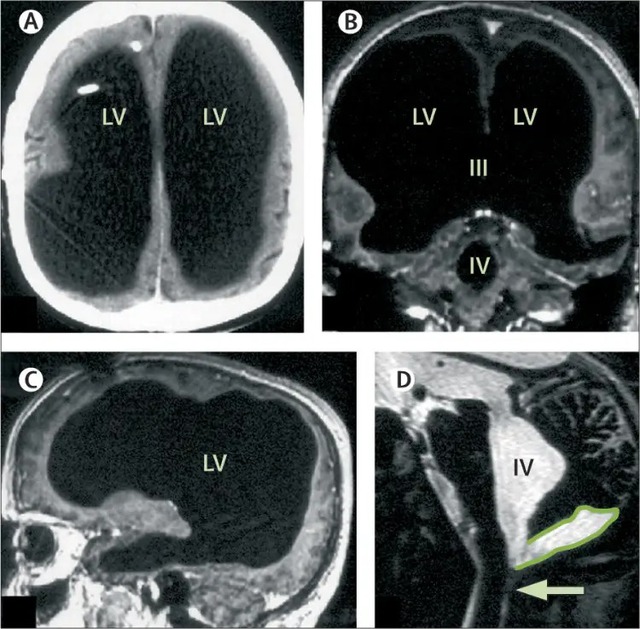

Những tưởng bệnh đã được khắc phục, nhưng 30 năm sau, khi ông bước sang tuổi 44, tình trạng yếu chân trái tái phát. Các bác sĩ tại Bệnh viện Marseille (Pháp) chỉ định chụp CT và MRI, và kết quả đã khiến toàn bộ ekip y khoa sửng sốt: não của ông gần như biến mất. Khoảng 75% đến 90% mô não bị tiêu hủy, thay vào đó là các khoang rỗng chứa đầy dịch não tủy.

Những hình ảnh chụp cộng hưởng từ cho thấy các thùy trán, thùy đỉnh, thùy thái dương và thùy chẩm - những khu vực đảm nhiệm tư duy, ngôn ngữ, cảm xúc và thị giác đều teo lại thành một lớp mỏng bao quanh hộp sọ. Trong điều kiện bình thường, tổn thương ở những vùng này sẽ dẫn đến suy giảm nghiêm trọng nhận thức, trí nhớ hoặc thậm chí rơi vào trạng thái sống thực vật.